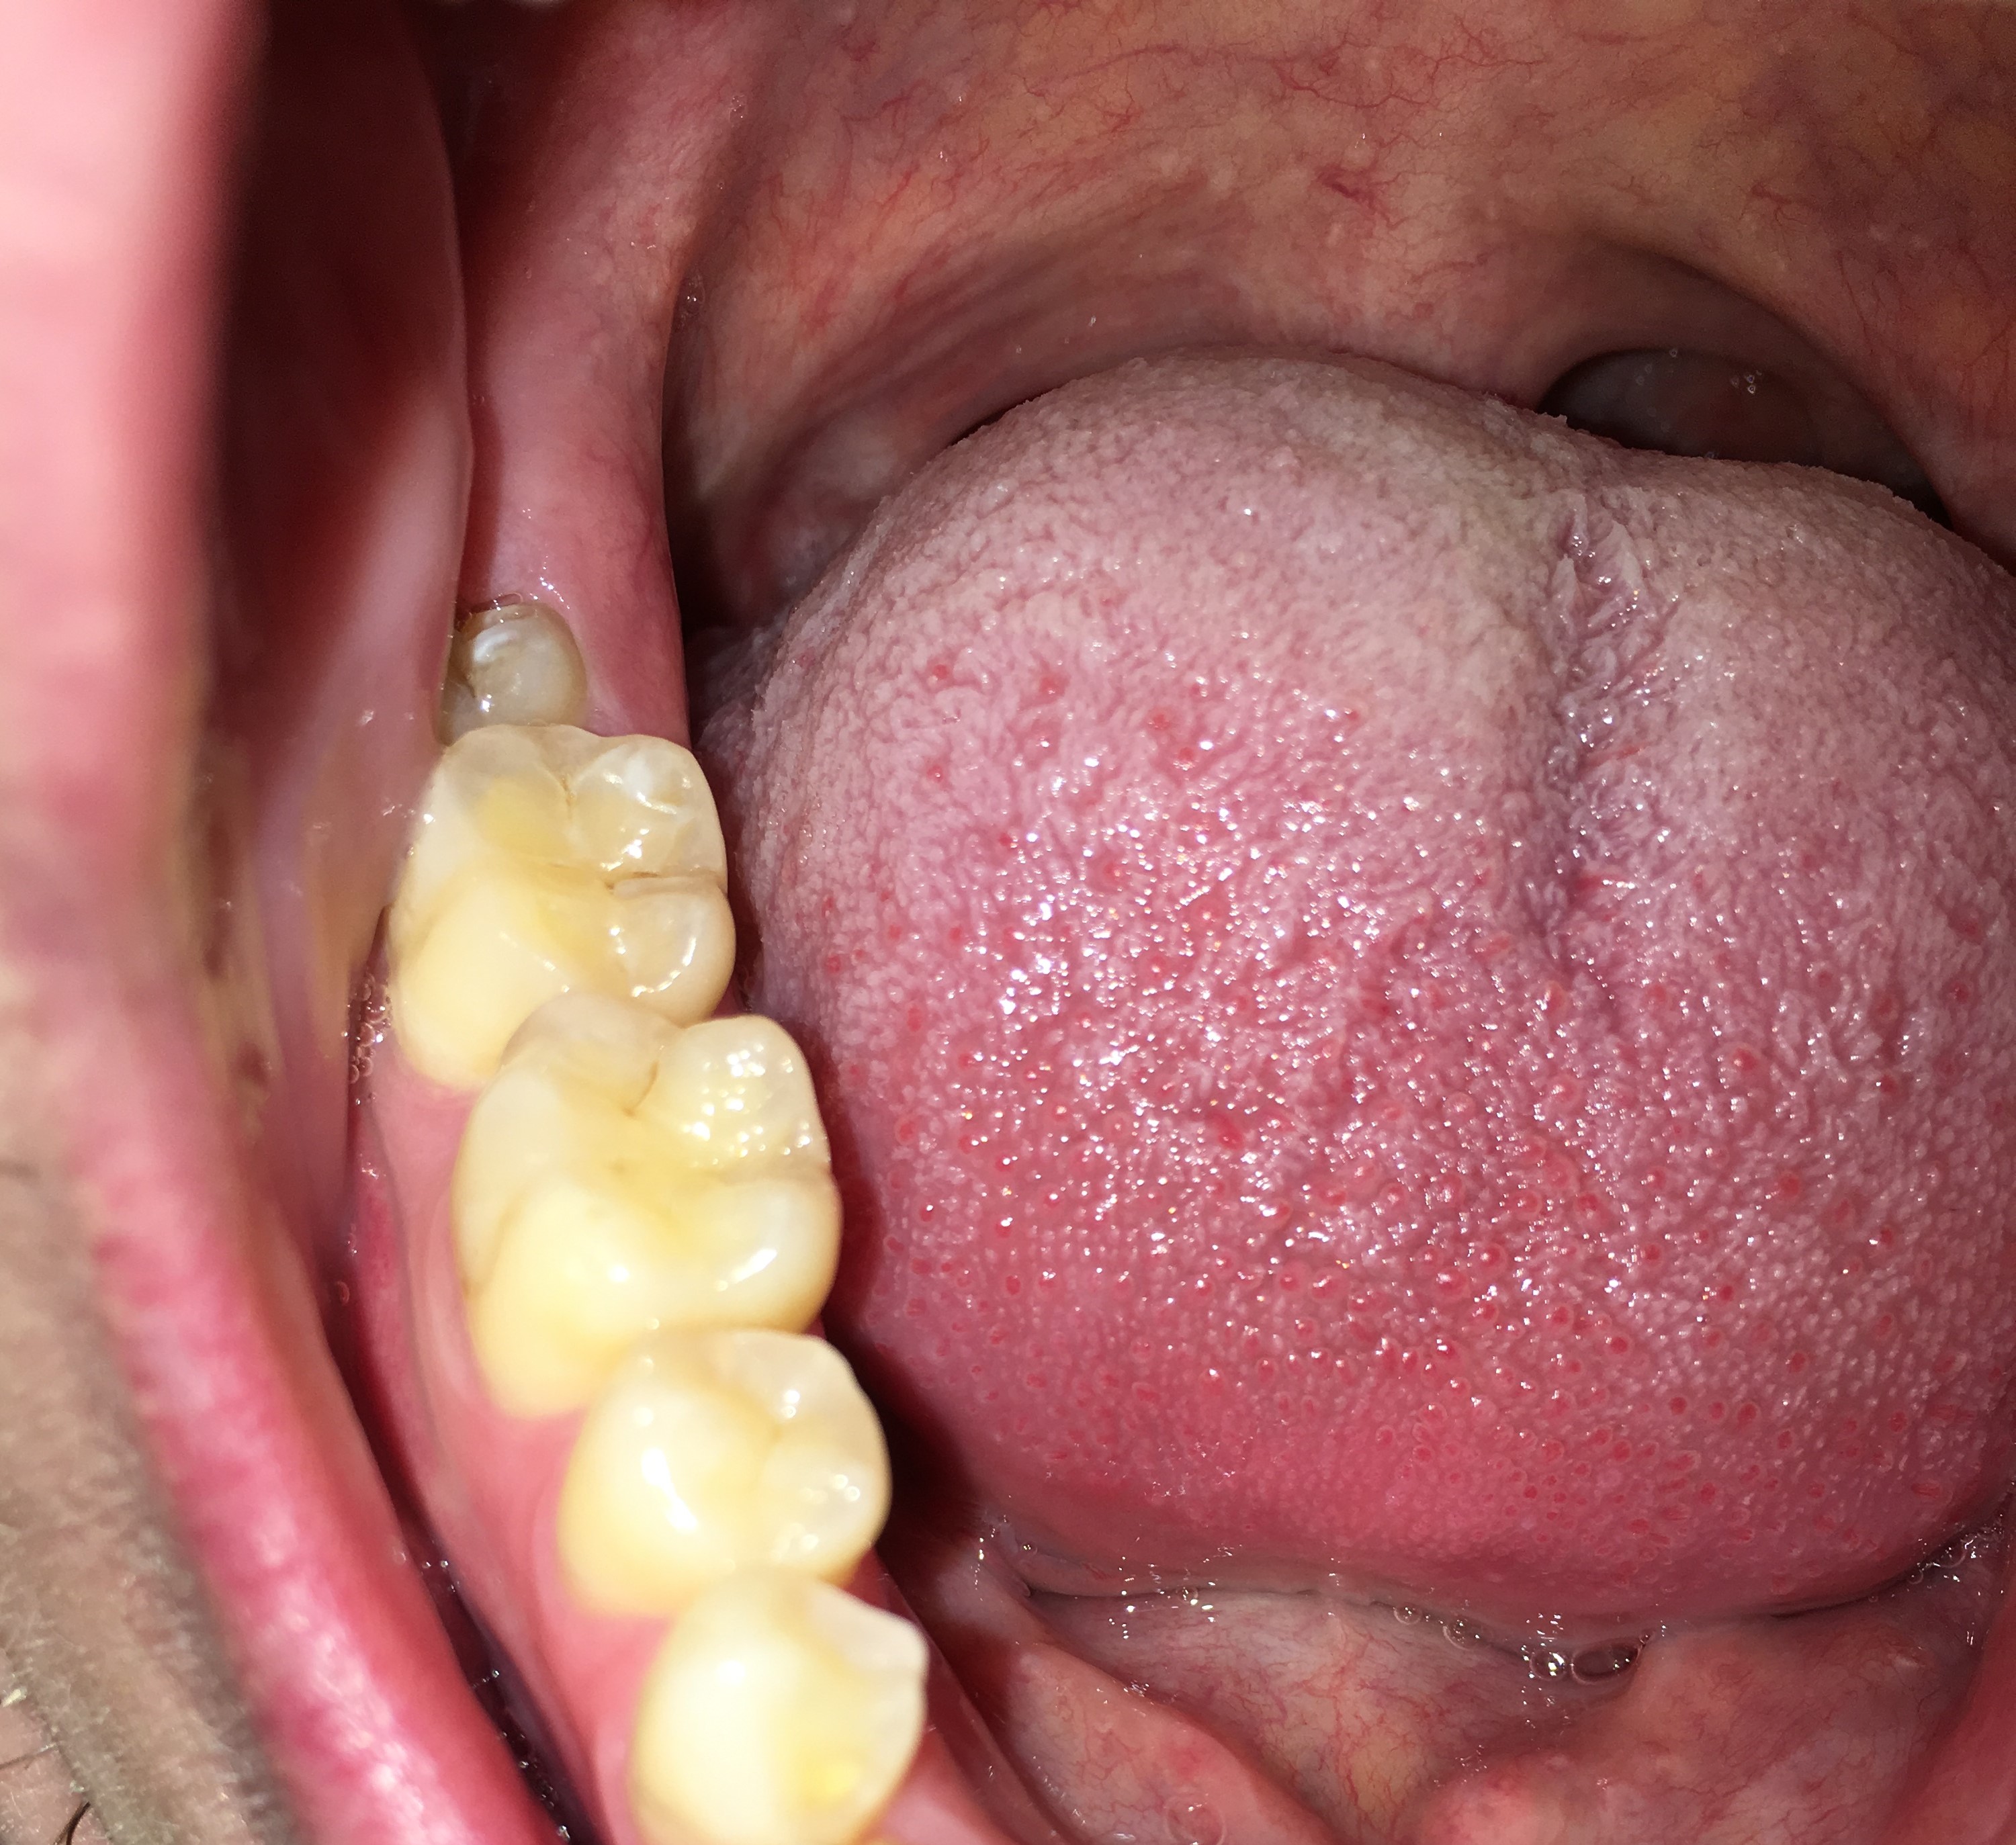

Ik zie dat de randen van mijn tanden en kiezen best doorzichtig zijn en las dat dit tanderosie kan zijn, daarnaast zie ik de dentine. Ik nuttig geen suikers of zuren dus ik begrijp niet waarom ik dit zou hebben. Daarnaast heeft de tandarts er nooit wat over gezegd. De eerste foto is van vandaag, de andere van 2015 (foto's van de boventanden). Als ik deze twee foto's vergelijk zie ik dat er geen verschil is en dat bij beide foto's evenveel doorzichtigheid en dentine te zien is.

De laatste foto is ook van vandaag, van de ondertanden. Moet ik me zorgen maken?

Nee, ook niet echt in mijn tienerjaren. Mijn tandarts of mondhygiënist hebben er nooit wat over gezegd, maar op andere (buitenlandse) online forums wordt door tandartsen gezegd dat er inderdaad sprake is van erosie. Ben een beetje geschrokken omdat ik geen frisdranken of koolzuurhoudende dranken nuttig. Als u zo naar de foto's kijkt, met name de eerste en tweede foto waar 10 jaar tussen zit. Zou je dan kunnen zeggen dat het gelijk is gebleven?

De tweede foto v d bovenkaak is niet duidelijk en voor de onderkaak is geen tweede vergelijking. Hoe is de PH v uw speeksel, wat eet u ...v zoveel factoren afhankelijk. Enige wat ik zie is dat u vrij doorzichtige tanden/kiezen heeft Dat hoeft niet negatief te zijn.

De tweede foto is inderdaad niet heel scherp, maar als je goed kijkt zie je dezelfde doorzichtigheid (heb een foto met pijltjes toegevoegd). Ik eet best gezond en mondhygiëne is ook best goed, ik vermijd suikers en drink voornamelijk water. Geen idee wat de PH is helaas, vind het ook apart dat mijn tandarts er nooit wat over heeft gezegd.

Hierbij 3 foto's van mijn onderkaak. De eerste foto is van mijn linker onderkaak van 2017, de tweede foto is van mijn rechter onderkaak van 2017 en de laatste foto is van 2015 van mijn gehele onderkaak. De foto van 2015 is met een andere telefoon genomen, hierdoor is de kleur en belichting wat anders, echter zie ik bij alle drie de foto's en de foto van 2025 de zelfde hoeveelheid doorzichtigheid.